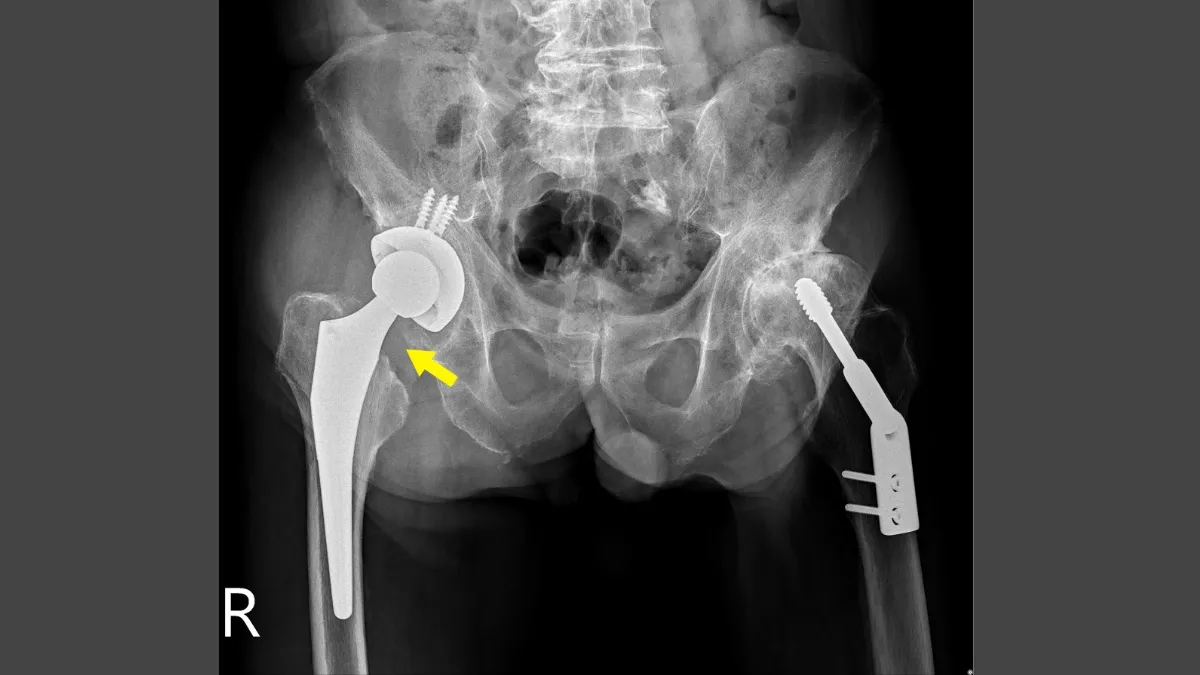

直到母親日前過世,施先生再次就醫時,髖關節已形成極大的磨損與壓迫。X光影像看到髖關節軟骨幾乎消失、關節處骨頭黏在一起、股骨頭磨損到扁平狀,只剩下一半,就像盤子一樣。洪舜奕醫師解釋,施先生的右腳因髖關節過度磨損,導致骨頭頭部只剩下一半,關節向上移位,造成步態不穩,無法久站。

洪舜奕醫師強調,腰部與髖部疼痛並延伸至鼠蹊部方向,同時伴隨無法遠走與久站,但膝蓋卻沒有不適,這是典型的髖關節退化表現。施先生已到腿部變形左O右直的長短腿情況,加上照顧母親的負重損傷,以及左腿舊傷的代償保護機制,身體多年慣性將重心加諸於右側,多重因素讓病灶加倍磨損。從檢查影像可推斷,退化疼痛症狀已困擾施先生多年,隱忍之下才如此嚴重。

針對施先生的嚴重磨損,洪舜奕採取了「前外側式人工全髖關節置換術」,置換四件套組以取代退化的關節。手術重點在於清除骨刺、切除破損部位,並換上耐磨墊片及人工股骨頭。手術時間約一至一個半小時,可調整雙腳長度,恢復正常。